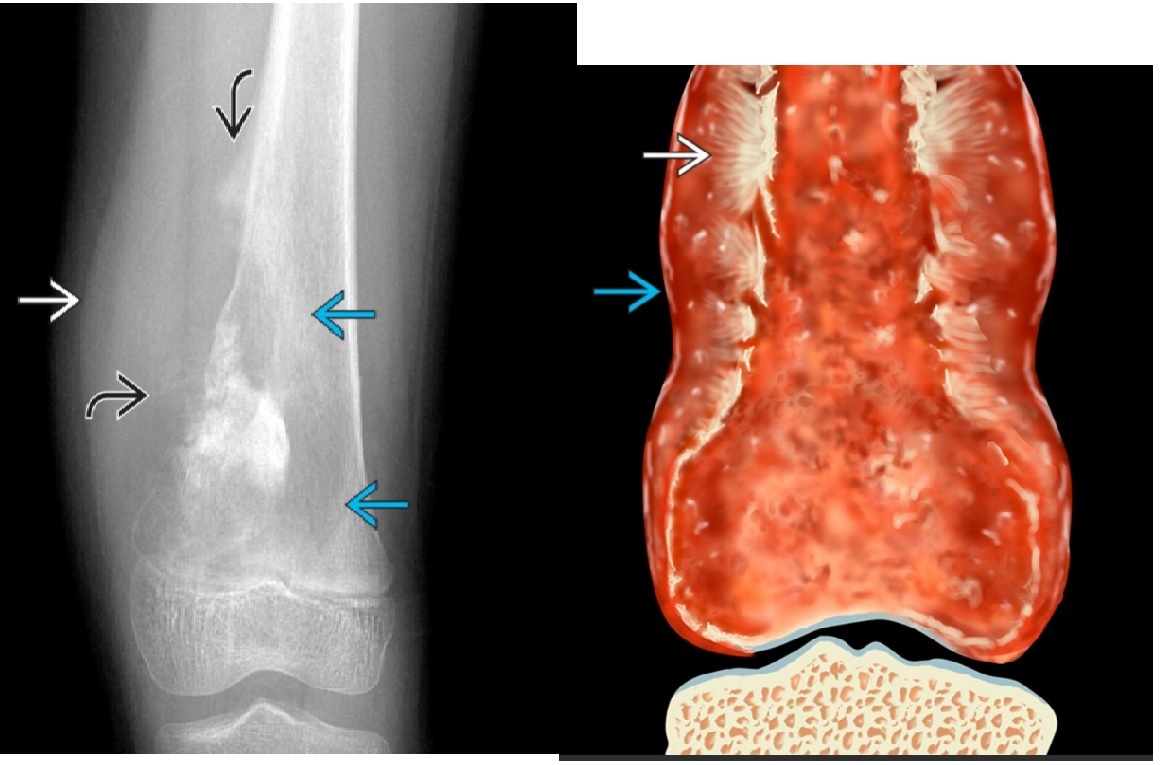

GCT -Physis closed. -Non-sclerotic margins -originated in epiphysis and extends to metaphysis. -Abuts articular surface -Eccentric -'Soap bubble' If in spine = **sacrum** Fluid-fluid level on MRI Can be locally aggresive, rarely metastases DDx +Chondroblastoma - Skeletal immature usually - originates in epiphysis rather than metaphysis - chondroid matrx - Sclerotic margin common + periosteal reaction -Extensive regional edema +Chondrosarcoma +ABC